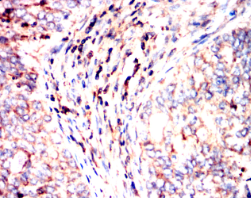

PIK3CA Mouse Monoclonal antibody[4F3A6]

PIK3CA is the most mutated gene in breast cancer and is important in other cancers. An integral part of the PI3K pathway, PIK3CA is an oncogene with two hotspots for activating mutations: the 542/545 region of the helical domain and the 1047 region of the kinase domain. The interaction of PIK3CA with the AKT and mTOR pathways is the subject of an immense amount of research and development, and PI3K inhibitors have exhibited some success in recent clinical trials. While PI3K monotherapies are likely insufficient, there is interest in pursuing PI3K inhibition in combination with other therapies including TKI's, MEK inhibitors, PARP inhibitors, and - in breast cancer - aromatase inhibitors.

IHC    1/200 - 1/1000